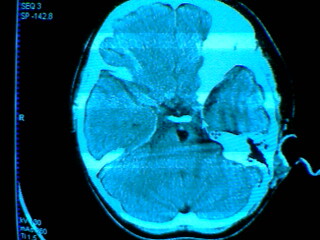

发热2天 无咳嗽咳痰 抽搐数次 现浅昏迷

其它层面无异常表现 故未上传

考虑:左侧桥小脑角池、基底池表皮样囊肿可能性大。

左侧桥小脑角池表皮样囊肿可能性大,部分突入桥前池,引起脑干受压